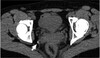

What is the dotted and solid arrow pointing to?

Dotted arrow: Kidney stone (urolith) Solid arrow: Phleboliths